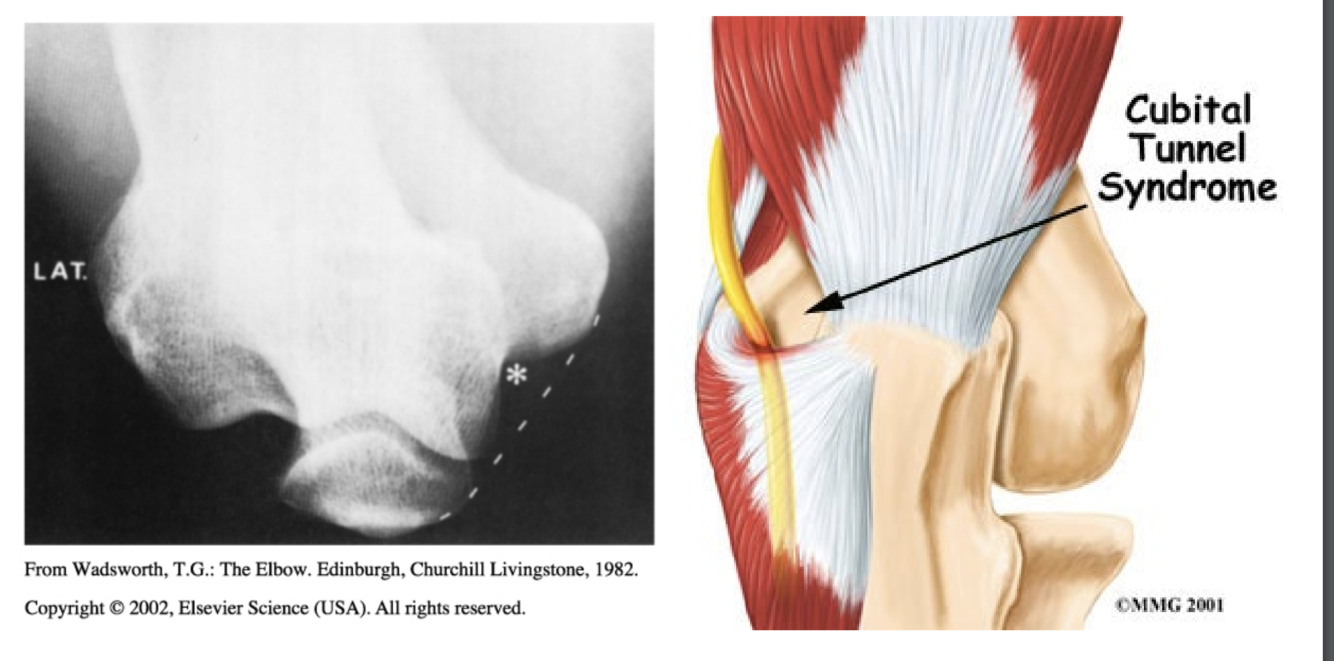

Ulnar Nerve Entrapment - Cubital Tunnel

Aetiology:

Clinical Presentation: